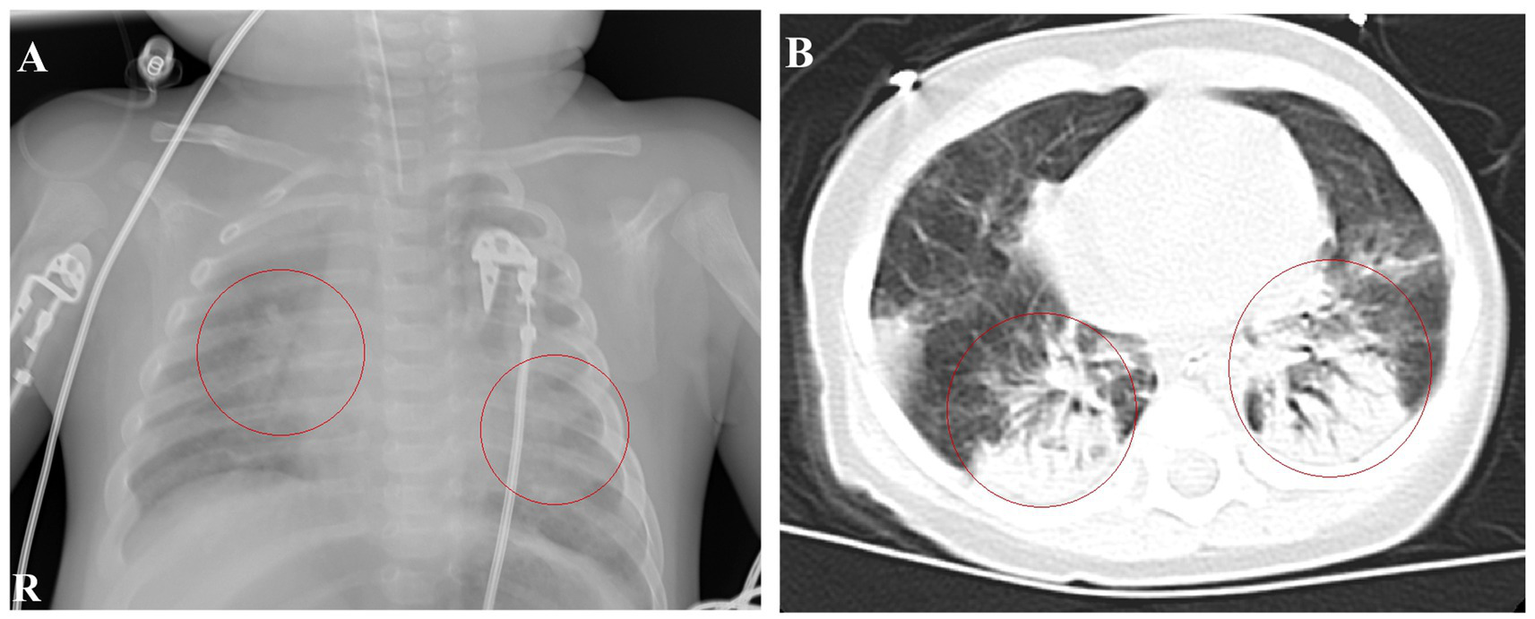

Upon admission, the patient had a body temperature of 38.7°C, heart rate of 200 beats per min, respiratory rate of 60 breaths per min, and blood pressure of 80/56 mmHg (1 mmHg = 0.133 kPa). He exhibited restlessness, cyanosis of the lips, nodding respiration, and inspiratory retraction. Bilateral lung auscultation revealed moist rales, a grade II systolic murmur in the precordial area, and a capillary refill time of <2 s. With mask oxygen inhalation, his SpO2 was 92%, as determined by pulse-oximetry. Chest radiography revealed multiple patchy shadows in both lungs (Figure 1A). Chest computed tomography showed multiple patchy hyperdense shadows in both lungs with air bronchogram (Figure 1B). Echocardiography identified an atrial septal defect measuring 2.5 mm. Cranial MRI showed no abnormalities. Routine blood examination revealed a white blood cell count of 60.41 × 109/L, lymphocyte count of 28.45 × 109/L, lymphocyte percentage of 0.471, neutrophil percentage of 0.425, hemoglobin level of 92 g/L, and platelet count of 677 × 109/L. High-sensitivity C-reactive protein (CRP) was measured at 63.99 mg/L. The procalcitonin level was 1.52 ng/mL. Bilateral peripheral blood cultures did not reveal bacterial growth after 5 days. Nucleic acid tests for B. pertussis and respiratory syncytial virus (RSV) in the sputum were positive, whereas tests for other respiratory pathogens were negative. Sputum culture did not reveal pathogenic bacteria growth after 5 days. Blood cytomegalovirus (CMV) DNA showed a concentration of 1.56 × 104 copies/mL, and urine CMV DNA was 7.71 × 102 copies/mL. Blood gas analysis revealed an oxygen tension of 58 mmHg, carbon dioxide tension of 50 mmHg, and sodium level of 132 mmol/L. Screening for renal function, humoral and cellular immunity, and genetic metabolic diseases showed no abnormalities. The patient received ventilator-assisted ventilation in pressure-control mode with a positive end-expiratory pressure of 4 cmH2O. The infant had a definite B. pertussis respiratory infection and was orally administered azithromycin (10 mg/kg/day, orally for 3 days and then stopped for 4 days for three courses). Meropenem (20 mg/kg, Q8H) and ambroxol were administered intravenously, and budesonide, ipratropium bromide, and acetylcysteine via nebulization.

Figure 1

Chest imaging at admission. (A) Chest radiograph on January 9th shows patchy shadows in both lungs. (B) Chest CT on January 10th reveals multiple patchy hyperdense and solid shadows.